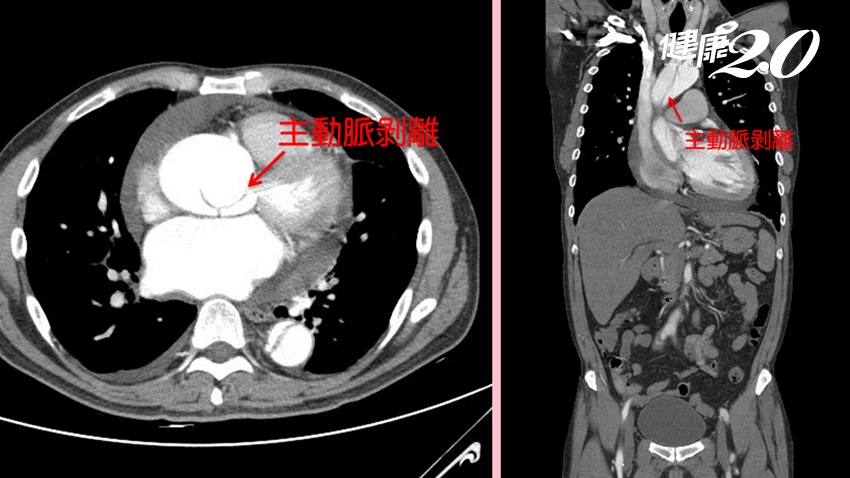

▲透過影像檢查可發現主動脈剝離的情況。

國泰醫院日前接到一名患者因洗澡時突然胸悶、暈厥而送來急診,因胸悶症狀及心肌酵素檢查顯示為急性心肌梗塞,使用抗擬血藥物後,進行心導管介入性檢查治療,才進一步發現同時有主動脈剝離現象,緊急手術後才搶回性命。